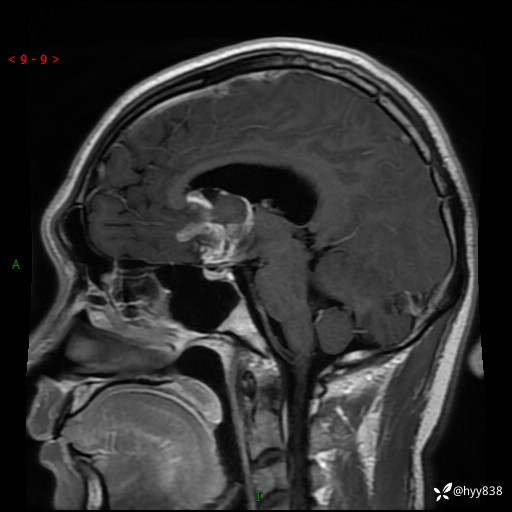

颅脑MRI平扫+增强